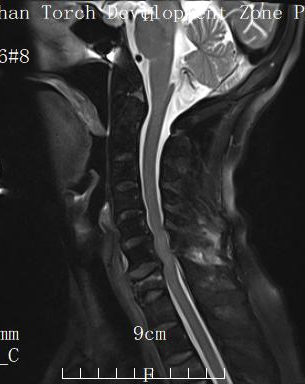

經(jīng)影像學(xué)檢查,確診為“頸7椎體骨折伴脊髓損傷”,且患者自身還患有糖尿病、高血壓等多種基礎(chǔ)疾病,身體機(jī)能及手術(shù)耐受性較差。

術(shù)后MRI